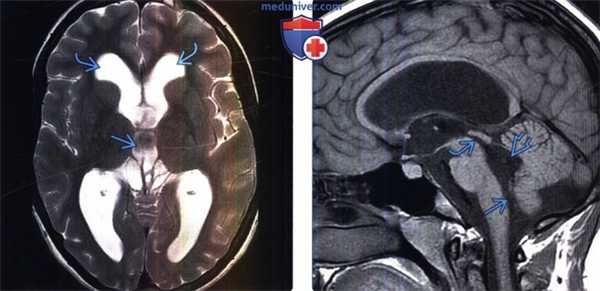

(Слева) Бесконтрастная КТ, аксиальный срез: в базальных цистернах, а также в сильвиевых бороздах определяется острое субарахноидальное кровоизлияние. Кроме того, отмечается внежелудочковая обструктивная гидроцефалия на ранней стадии ее развития с легким снижением плотности мозговой ткани в перивентрикулярных отделах вследствие интерстициального отека.

(Справа) МРТ, постконтрастное Т1-ВИ, аксиальный срез: определяется протяженное контрастирование лептоменинкс в базальных цистернах при нейросаркоидозе. Обратите внимание сообщающуюся гидроцефалию на ранней стадии ее развития с расширением III желудочка и височных рогов боковых желудочков.

(Слева) МРТ, Т2-ВИ, аксиальный срез: у пациента 21 года с давно перенесенным менингитом в анамнезе определяется хроническая «компенсированная» внежелудочковая сообщающаяся гидроцефалия с выраженным расширением боковых желудочков и III желудочка.

(Справа) МРТ, Т1-ВИ, сагиттальный срез: у того же пациента отмечается очевидное расширение водопровода мозга и отверстия Маджанди с расширением IV желудочка. При длительной «компенсированной» гидроцефалии перивентрикулярный интерстициальный отек, как и в данном случае, отсутствует.